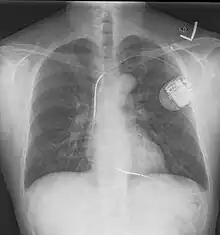

A chest radiograph showing bronchopulmonary dysplasia. A chest film after insertion of an implantable cardioverter-defibrillator, showing the shock generator in the upper left chest and the electrical lead inside the right heart. Note both radio-opaque coils along the device lead.

A chest film after insertion of an implantable cardioverter-defibrillator, showing the shock generator in the upper left chest and the electrical lead inside the right heart. Note both radio-opaque coils along the device lead.